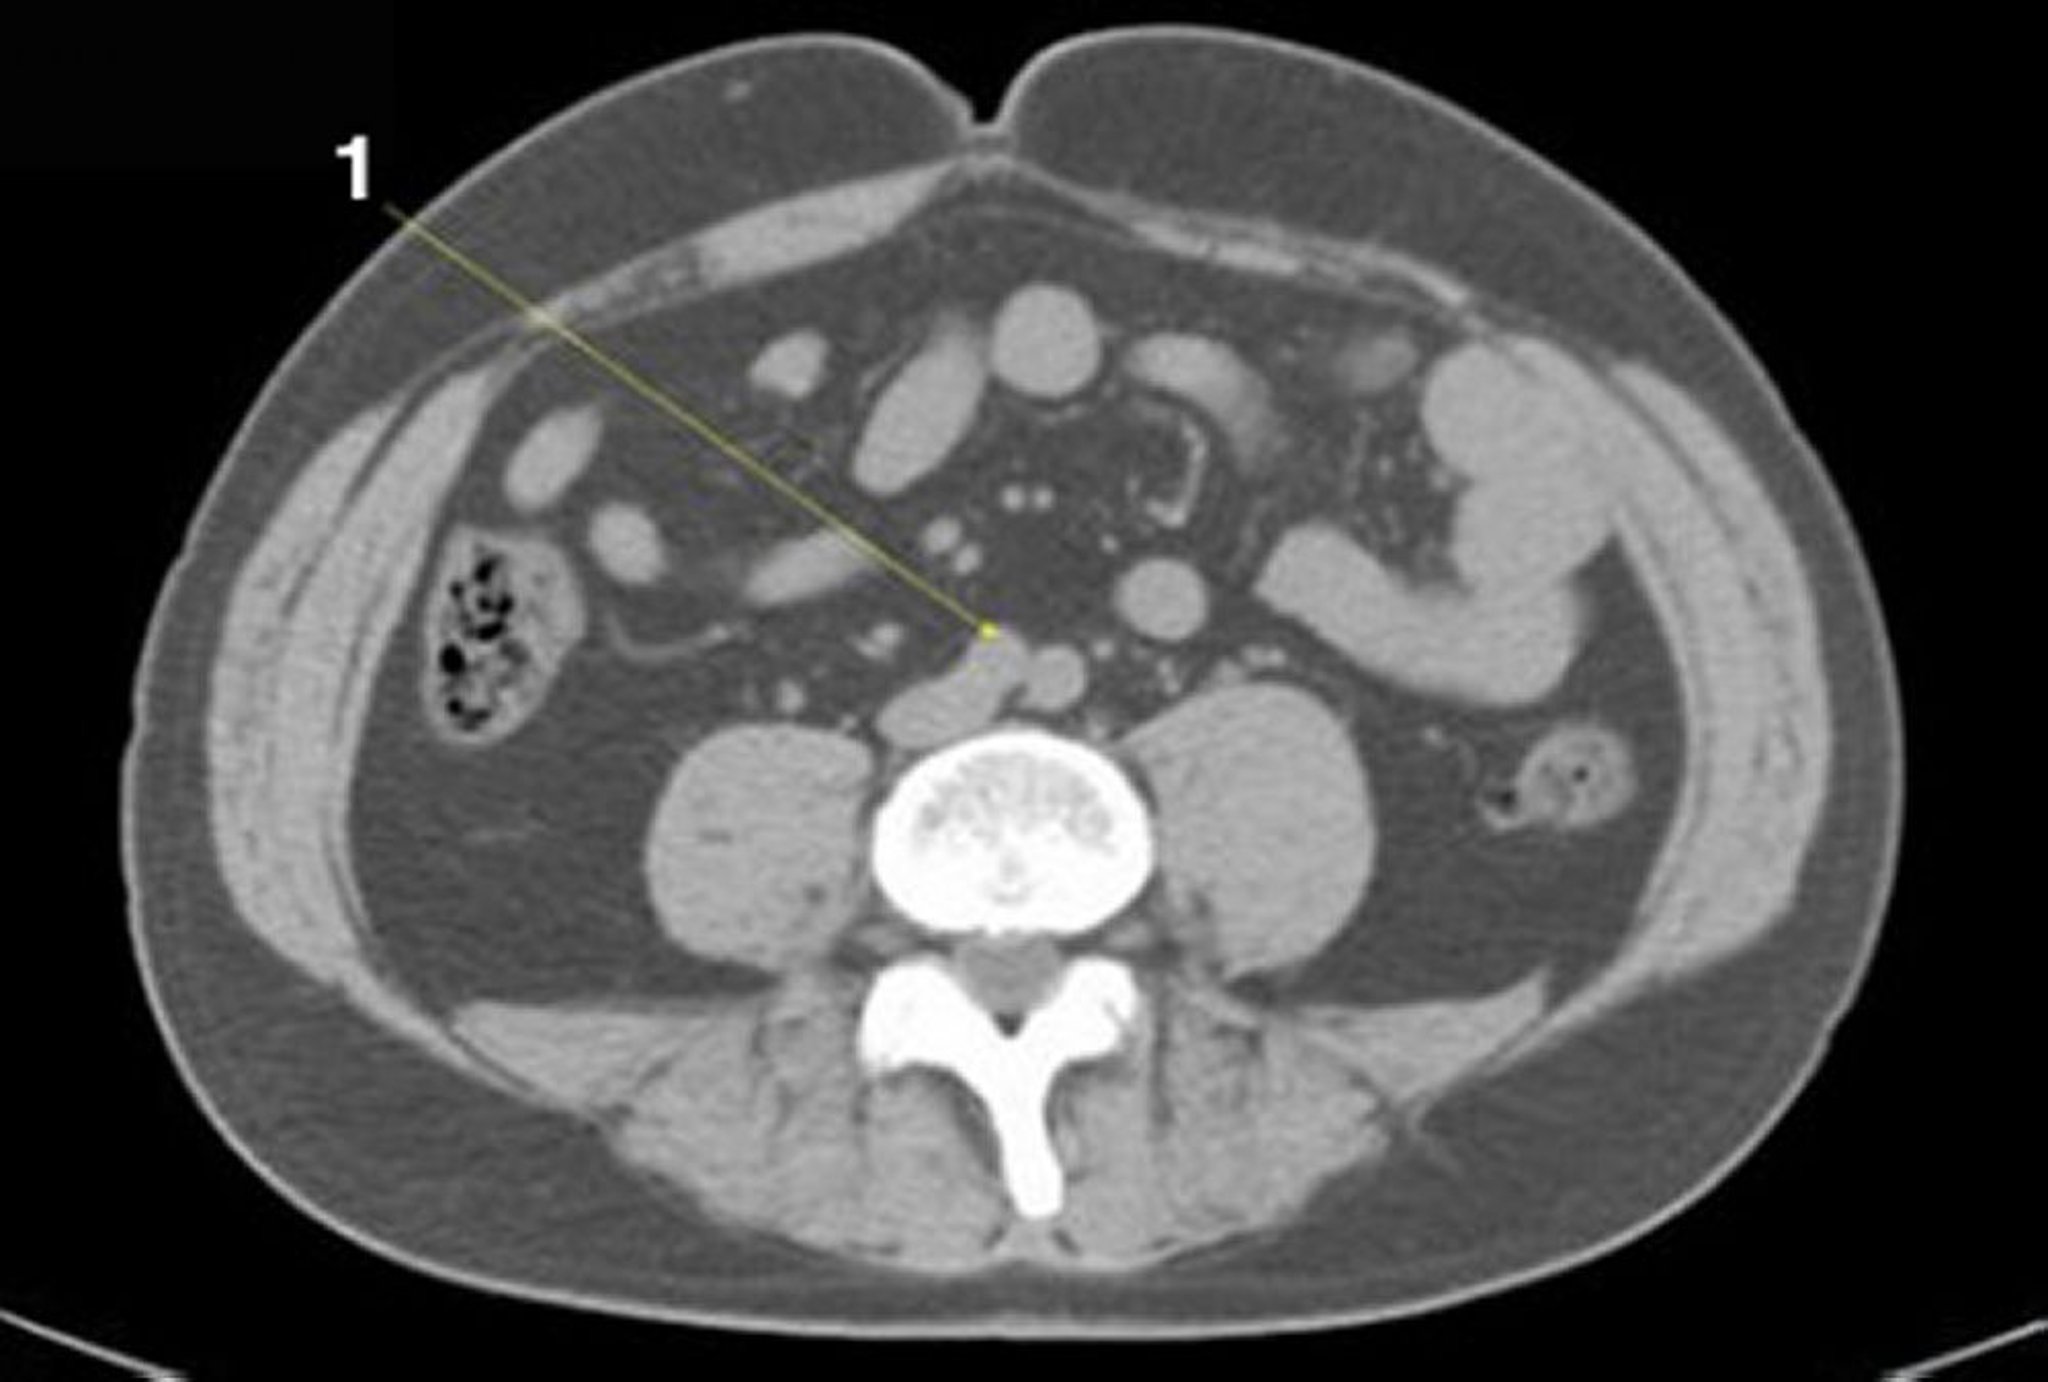

正常解剖を示した腹部および骨盤の単純CT画像(スライド20)

1 = 大動脈分岐部。